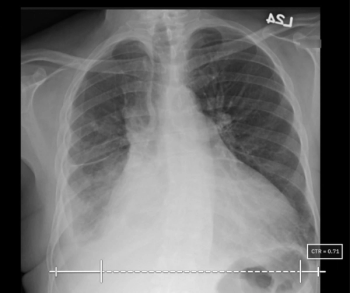

Leveraging artificial intelligence (AI) algorithms, the qXR-CTR reportedly provides automated cardiothoracic ratios (CTRs) through assessment of plain chest radiographs.